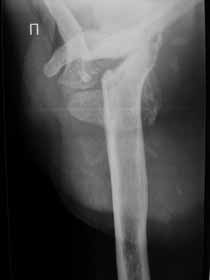

Re: Лизис костей плечевого сустава

Извиняюсь, что-то фотографии сразу не прошли. сейчас исправимся.